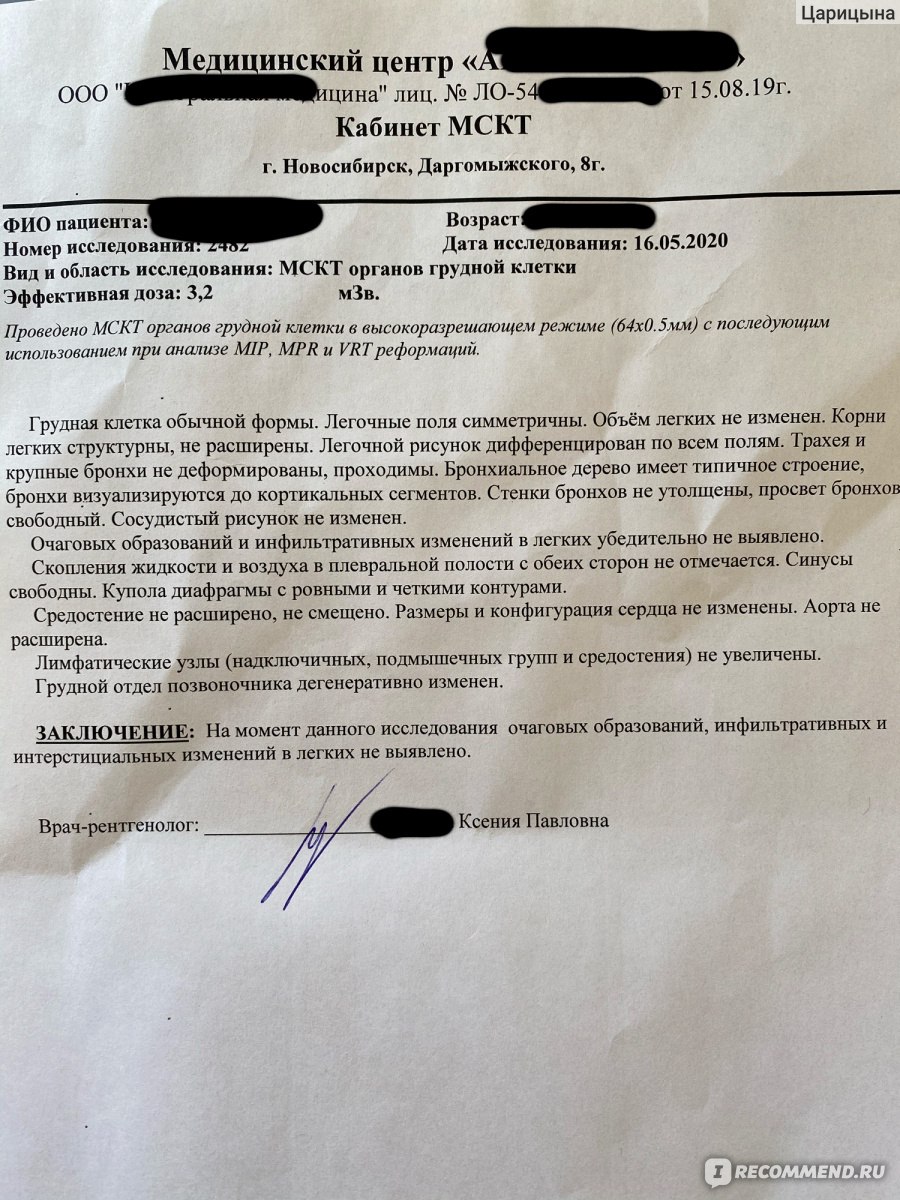

Фотографии и снимки КТ легких без контрастных веществ

Раздел: Визуальный дайджест